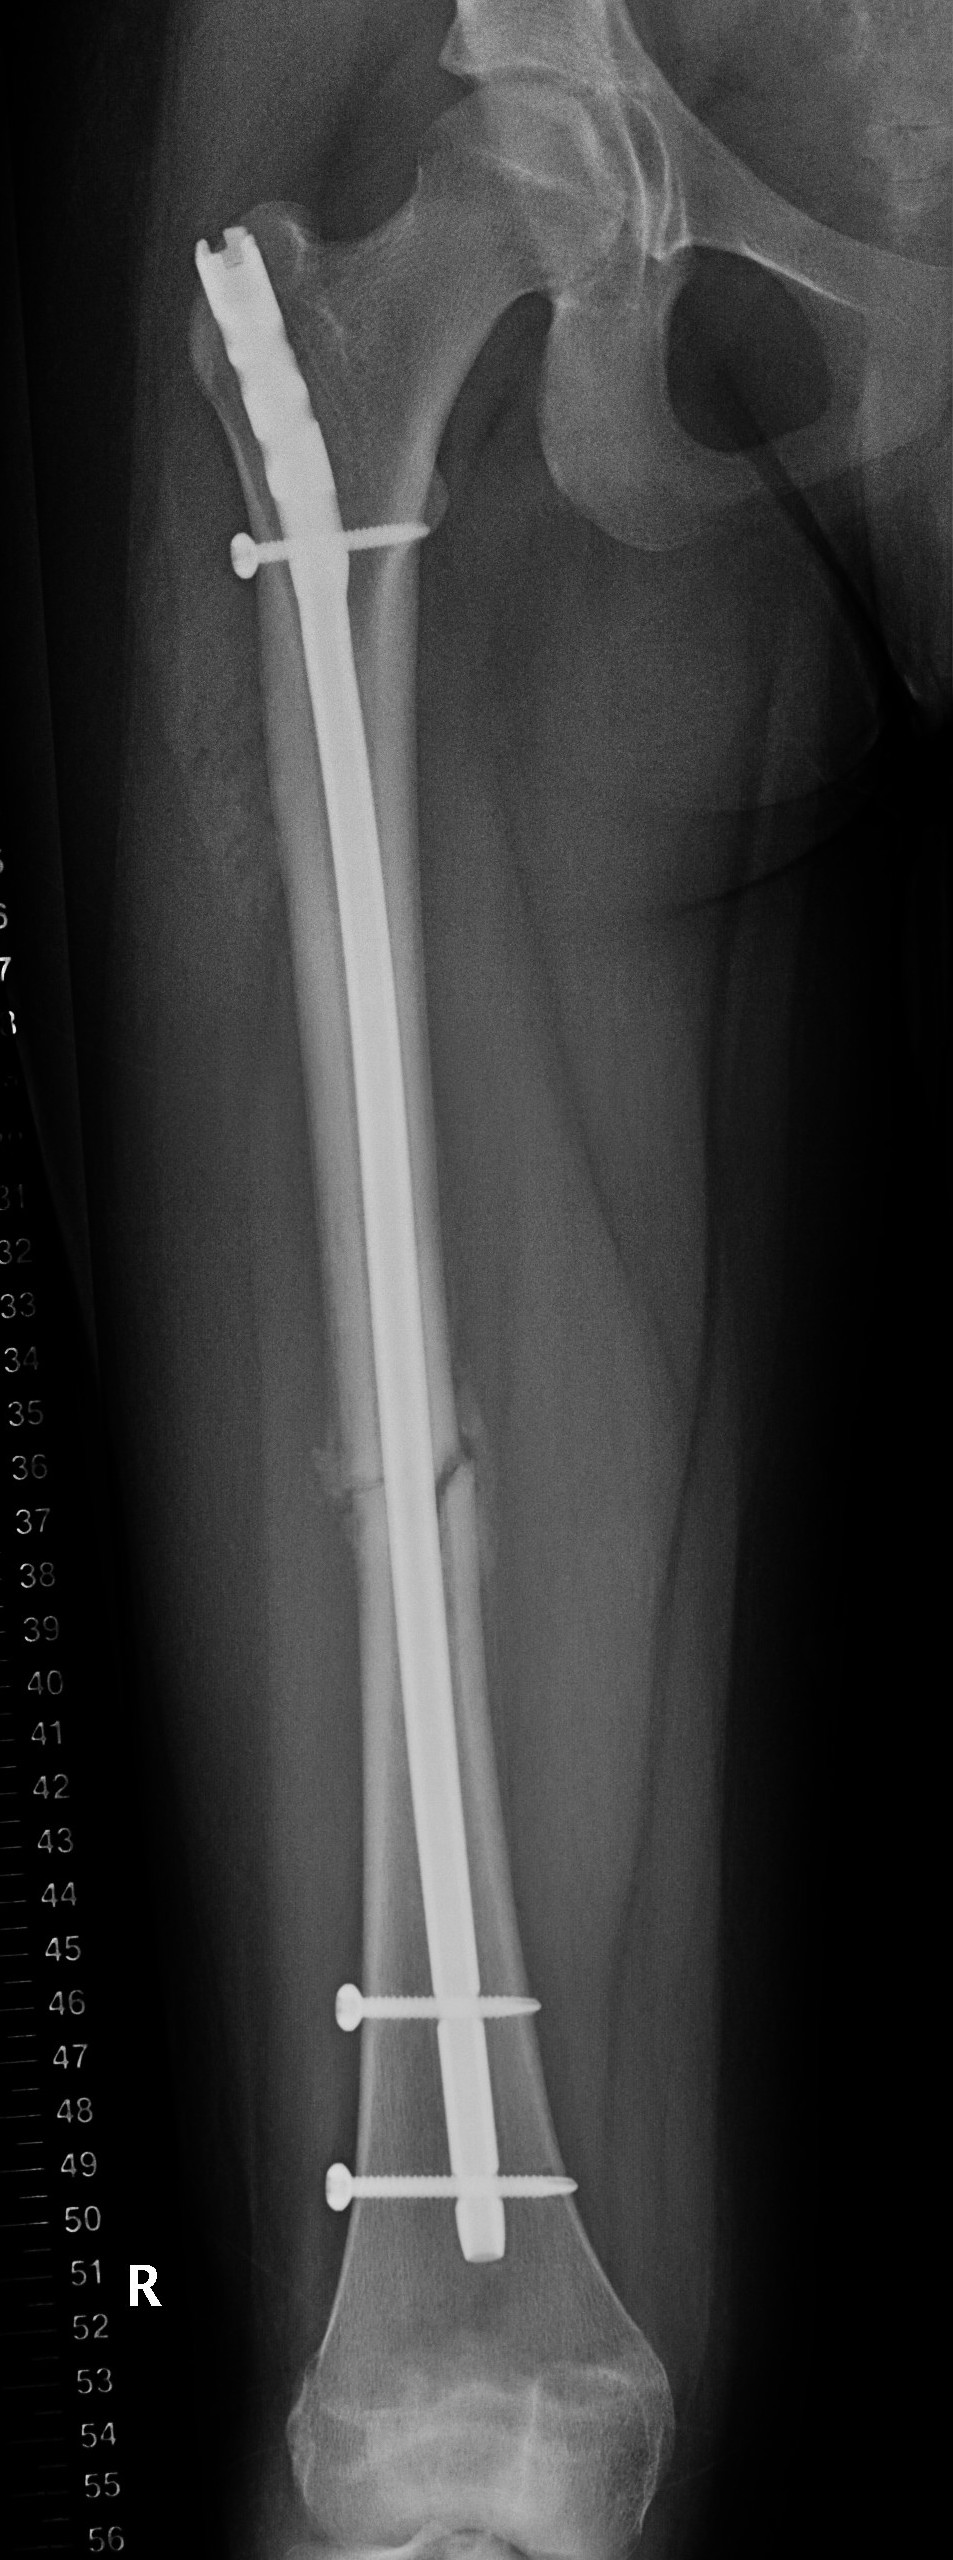

Femur plates

Indication

- length unstable fractures (spiral / comminuted)

- distal or proximal fractures

Options

Open plating

Submuscular bridge plating

Abott et al. J Paediatr Orthop 2013

- comparison of open v submuscular bridge plating in 79 patients

- increased blood loss in open plating

- increased rotational asymmetry in bridge plating

- no other difference between two groups

Technique

- supine on radiolucent table or traction table

- proximal and distal incisions

- blunt dissection to periosteal layer

- run bristow or cobb elevator submuscularly

- 3.5 or 4.5mm LCP plate submuscularly

- indirect reduction techniques

- if inadequate reduction need to open